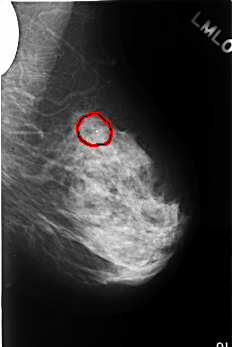

C_0379_1.LEFT_MLO

LEFT_MLO LINES 4504 PIXELS_PER_LINE 3016 BITS_PER_PIXEL 12 RESOLUTION 50 OVERLAY

FILE: C_0379_1.LEFT_MLO.OVERLAY

TOTAL_ABNORMALITIES 1

ABNORMALITY 1

LESION_TYPE CALCIFICATION TYPE PLEOMORPHIC DISTRIBUTION CLUSTERED

ASSESSMENT 4

SUBTLETY 5

PATHOLOGY BENIGN

TOTAL_OUTLINES 1

BOUNDARY